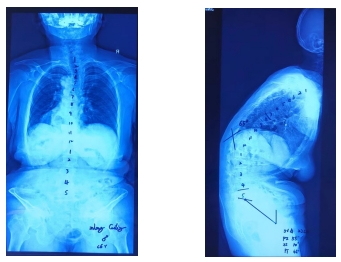

脊柱全长正侧位片:

术前评估矢状面及冠状面,SVA:22cm、CBD:2cm、冠状面Cobb角:14°、TPA:65°、GK:65°、TLK:42°、LL:-16°、PI:55°、SS:10°、PT:45°。经过多学科会诊及科室内讨论,对潜在风险、替代治疗方案系统评估后,患者接受了胸8至骶骨的后路长节段融合手术,后路多节段Ponte截骨。手术采用3D打印导板和导航协助置钉,超声骨刀截骨,电生理监护神经功能,手术顺利,矫形满意。实施本次手术时,我们使用了三项新技术,第一项新技术是经骶2骶髂螺钉(S2AI)固定,固定坚强,恢复矢状面平衡,预防远端交界性后凸。第二项新技术是卫星棒的使用,用多棒和序贯的理念矫形,降低术后断棒的风险。第三项新技术是斜向钉的使用,螺钉向头侧穿过3层皮质,减少对近端软组织的损伤,预防近端交界性后凸。术后镇痛、理疗、药物DVT预防,早期康复锻炼。术后第4天拔除引流管后下地活动,术后第7天康复出院。患者下地活动后,腰部疼痛较术前明显好转,双下肢肌力提高至4+级,神经源性跛行得到缓解,部分恢复生活自理能力。术后评估矢状面及冠状面,SVA:3cm、CBD:2cm、冠状面Cobb角:8°、TPA:24°、GK:14°、TLK:9°、LL:43°、PI:53°、SS:19°、PT:34°。